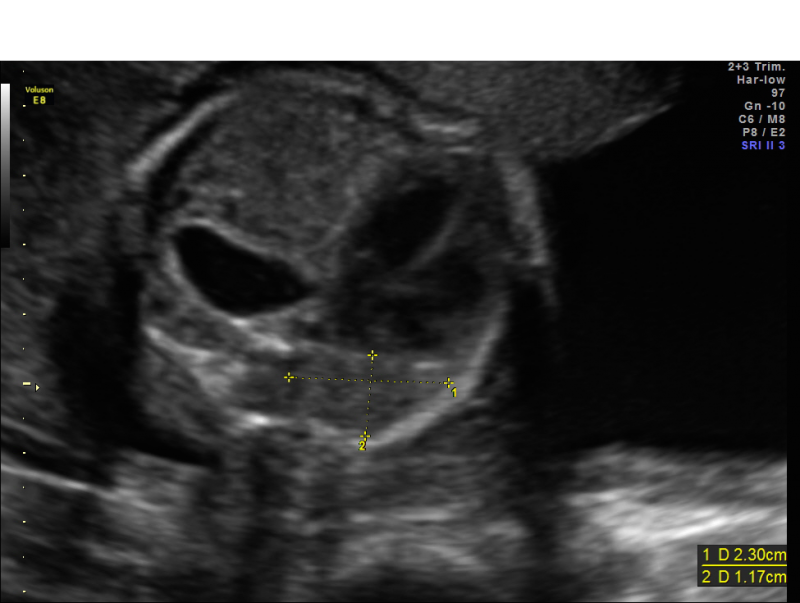

From mavink.com

Congenital Diaphragmatic Hernia Ultrasound Diaphragmatic Hernia Lhr In this condition, there’s an opening in your baby’s diaphragm. It allows some of the organs that should be found in your child’s belly to move up into the chest cavity. Congenital diaphragmatic hernia is a condition resulting from the herniation of abdominal contents into the thoracic cavity. 50% require extracorporeal membrane oxygenation (ecmo) and 50% die. Congenital diaphragmatic hernia. Diaphragmatic Hernia Lhr.

Fetal Diaphragmatic Hernia Ultrasound Diaphragmatic Hernia Lhr 1,500 babies are born with cdh; It allows some of the organs that should be found in your child’s belly to move up into the chest cavity. Key points about congenital diaphragmatic hernia. Congenital diaphragmatic hernia (cdh) is characterized by a defect in the diaphragm leading to the protrusion of abdominal contents into the thoracic cavity. 50% require extracorporeal membrane. Diaphragmatic Hernia Lhr.